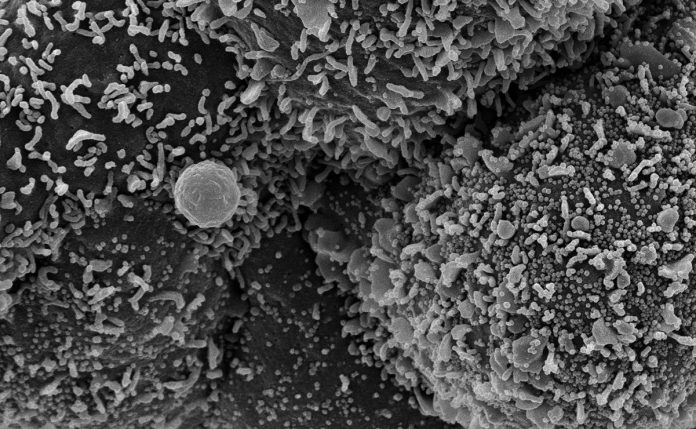

Sin embargo, si bien un estudio australiano publicado en abril de 2020 observó una eficacia in vitro (en laboratorio) de la invermectina contra el coronavirus SARS-CoV-2, esta no está demostrada en el hombre, puesto que hasta ahora los ensayos fueron limitados y con muchos sesgos.

Además, muy a menudo los tratamientos in vitro no pueden trasladarse al ser humano, especialmente porque no pueden administrarse las mismas concentraciones de medicamentos.